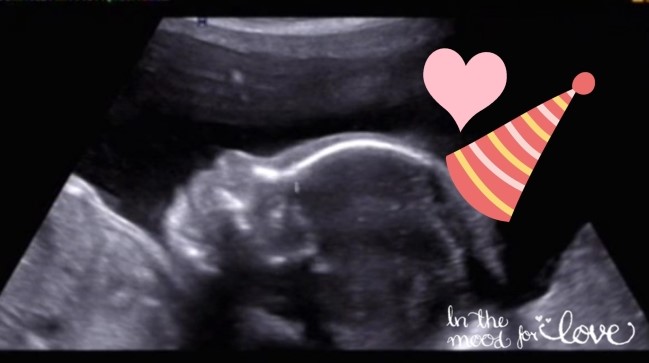

꼬기 입체초음파 (임신 26주 6일, 임신 7개월) 누구를 더 닮았나 ㅎㅎ

+ 꼬기 얼굴 보던 날 + 임신 26주 6일, 임신 7개월 입체 초음파 + 임당 검사 꼬기에 대한 기록은 밀...